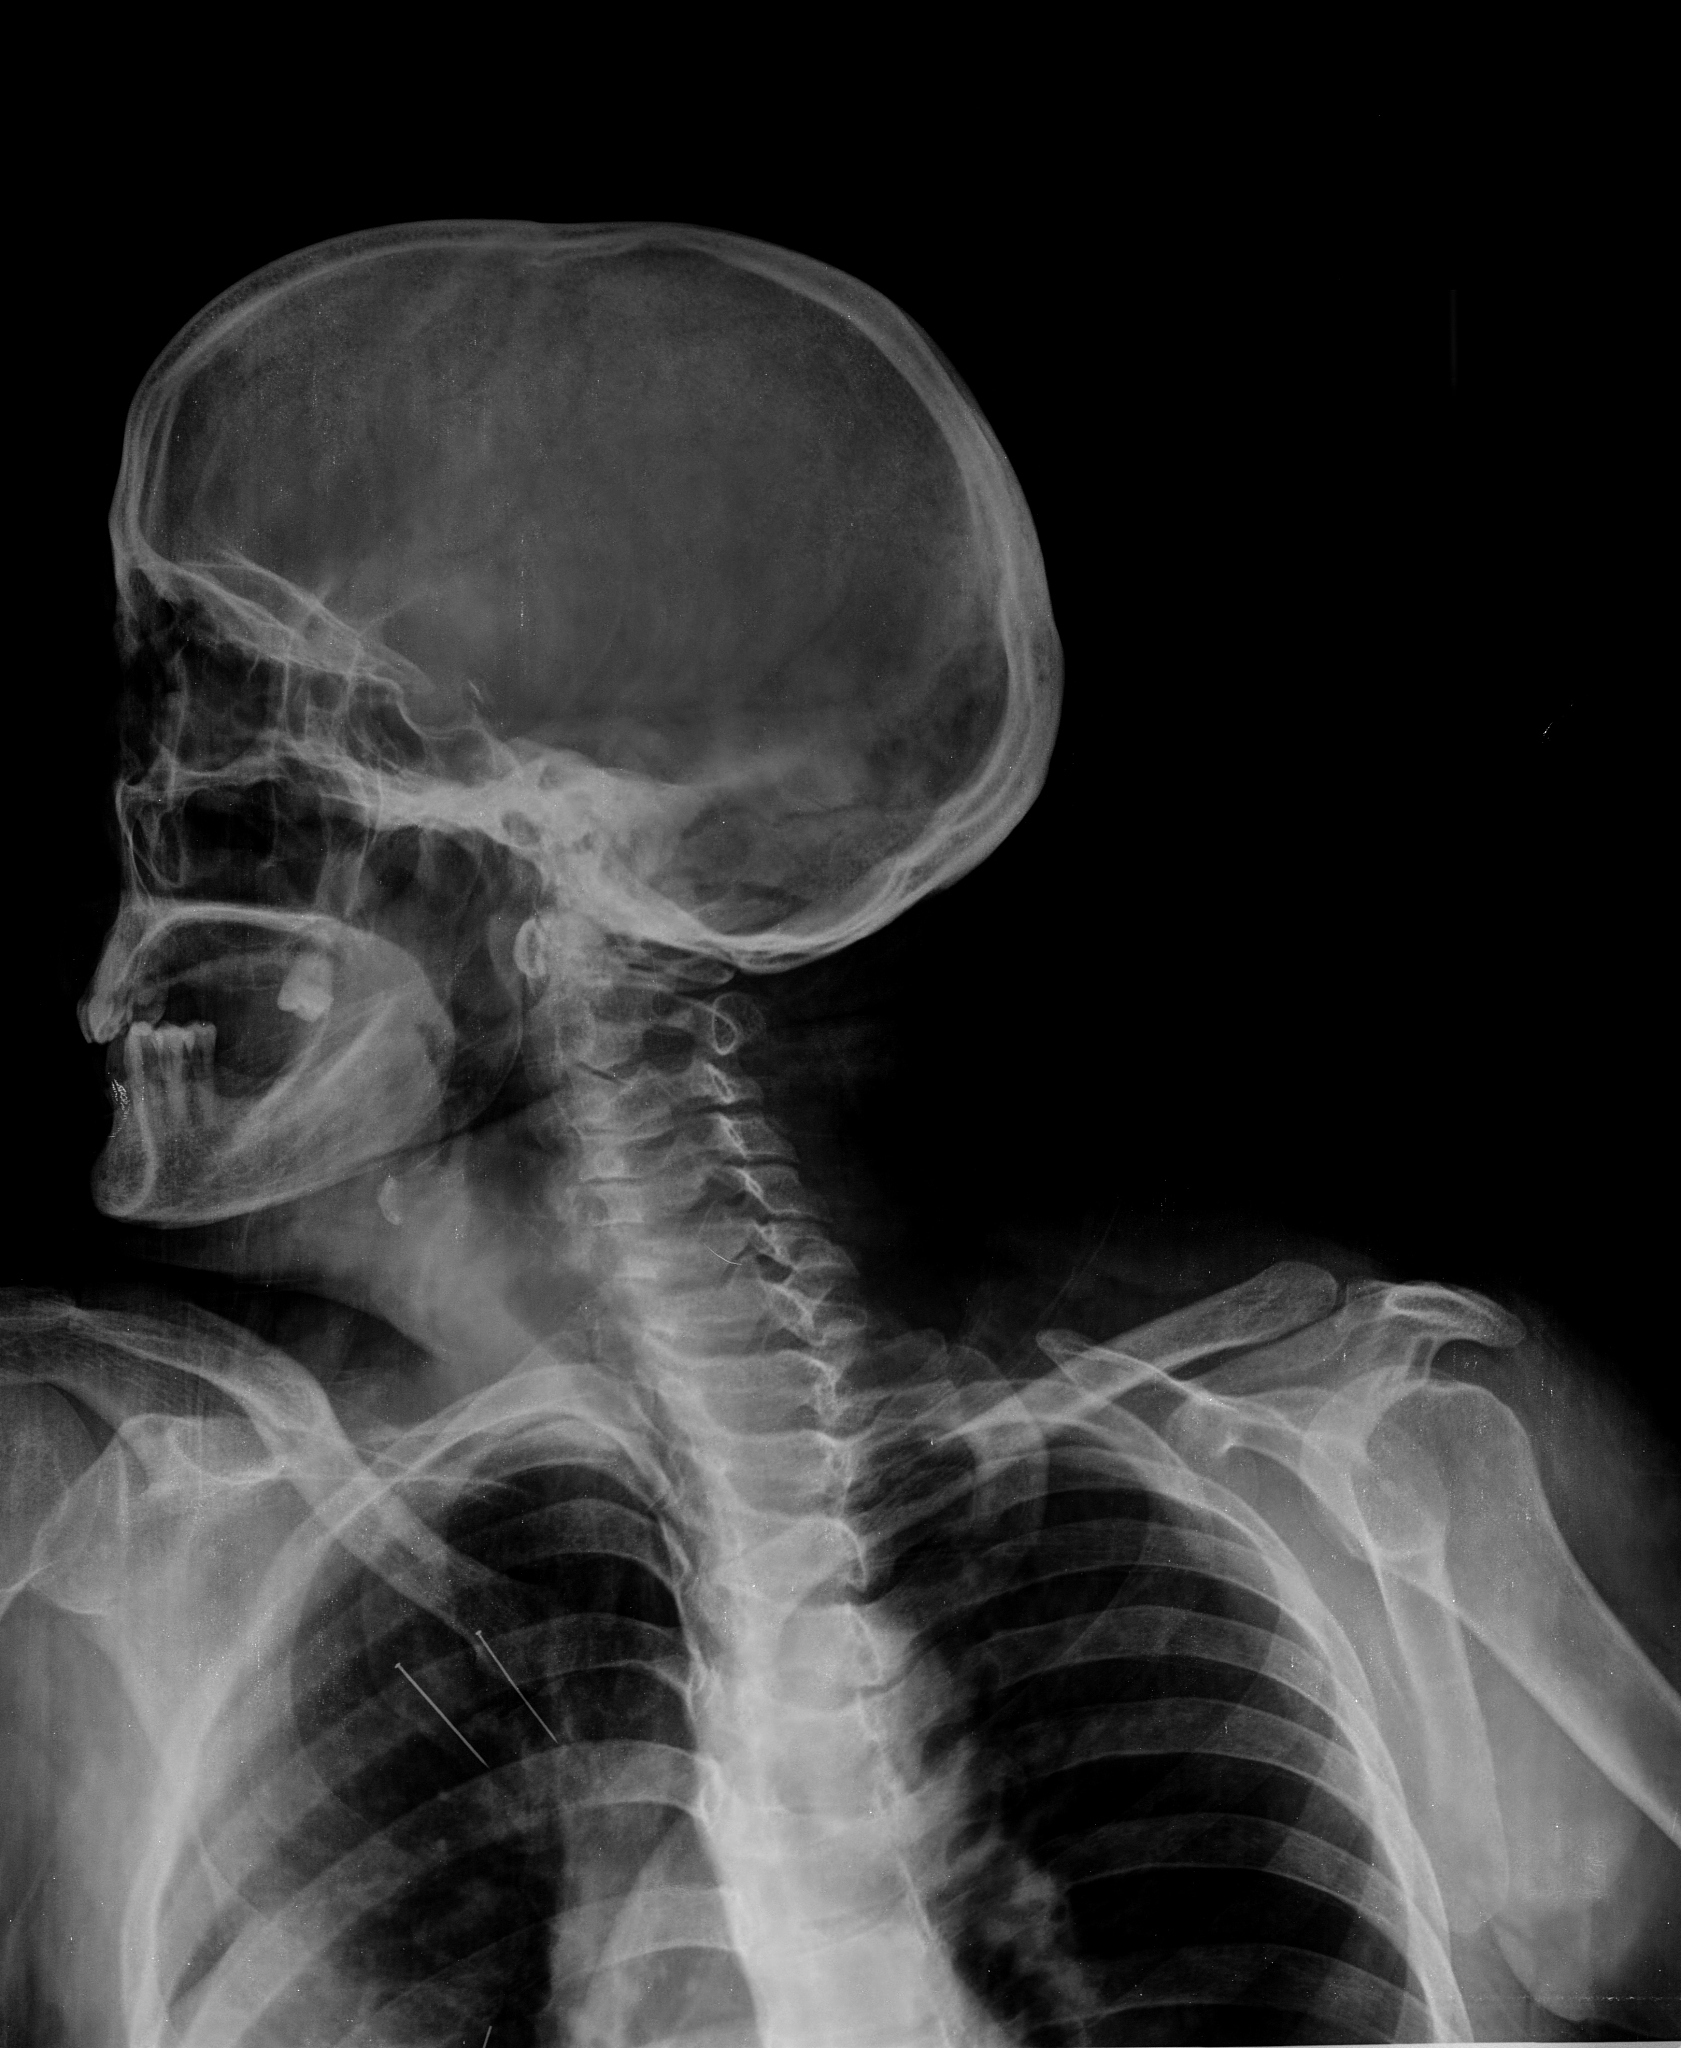

三凹征:误吸入物体后出现的三个部位凹陷

三凹征是指误吸入物体后,出现的三个部位的凹陷,包括:

颈部凹陷:误吸入物体后,由于气道堵塞,呼吸困难导致颈部呈凹陷状态。

胸骨下凹陷:误吸入物体后,呼吸肌肉的受限导致胸骨下部位凹陷。

肋间凹陷:由于气道堵塞,呼吸肌肉的受限导致肋骨之间的空隙凹陷。